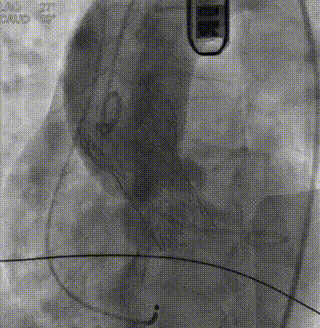

最终造影1

最终造影2

术后即刻超声,瓣膜与患者自身解剖结构贴合良好,无瓣周漏,跨瓣压差降为3mmHg,峰值流速降为1.32m/s,手术取得圆满成功。